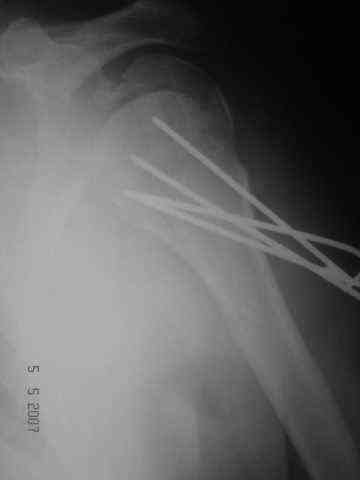

Dear all, A heavy built 30-year-old male patient sustained fracture dislocation of left shoulder about 8 months back.

For this ORIF with K-wires was done elsewhere. K-wires were removed at 6 weeks and patient advised physiotherapy. He has been doing physio dedicatedly since then.

Looking at his previous x-rays, I was thinking of refixing the greater tuberosity, however got anaxillary view done today which was never done during this period and this shows non-union.

It looks like the initial injury was a head splitting fracture. Presently the patient has a non-union at the level of the anatomical neck with displaced tuberosities. I would tackle the non-union, and would try to replace the tuberosities, a difficult procedure. I would use the proximal humerus locking plate from the AO.